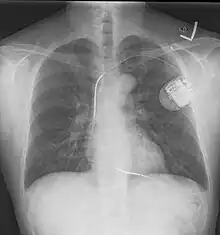

An implantable cardioverter-defibrillator (ICD) or automated implantable cardioverter defibrillator (AICD) is a device implantable inside the body, able to perform defibrillation, and depending on the type, cardioversion and pacing of the heart. The ICD is the first-line treatment and prophylactic therapy for patients at risk for sudden cardiac death due to ventricular fibrillation and ventricular tachycardia.[1]

The process of implantation of an ICD system is similar to implantation of a artificial pacemaker. In fact, ICDs are composed of an ICD generator and of wires. The first component or generator contains a computer chip or circuitry with RAM (memory), programmable software, a capacitor and a battery; this is implanted typically under the skin in the left upper chest. The second part of the system is an electrode wire or wires that, similar to pacemakers, are connected to the generator and passed through a vein to the right chambers of the heart. The lead usually lodges in the apex or septum of the right ventricle.[6]

Just like pacemakers, ICDs can have a single wire or lead in the heart (in the right ventricle, single chamber ICD), two leads (in the right atrium and right ventricle, dual chamber ICD) or three leads (biventricular ICD, one in the right atrium, one in the right ventricle and one on the outer wall of the left ventricle). The difference between pacemakers and ICDs is that pacemakers are also available as temporary units and are generally designed to correct slow heart rates, i.e. bradycardia, while ICDs are often permanent safeguards against sudden life-threatening arrhythmias.

Initially ICDs were implanted via thoracotomy with defibrillator patches applied to the epicardium or pericardium. The device was attached via subcutaneous and transvenous leads to the device contained in a subcutaneous abdominal wall pocket. The device itself acts as an electrode. Most ICDs nowadays are implanted transvenously with the devices placed in the left pectoral region similar to pacemakers. Intravascular spring or coil electrodes are used to defibrillate. The devices have become smaller and less invasive as the technology advances. Current ICDs weigh only 70 grams and are about 12.9 mm thick.